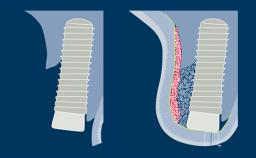

Surgical Planning and Procedures

Principles for the Management of Peri-Implant Defects

Learning Module

Surgical Planning and Procedures

Principles of Guided Bone Regeneration (GBR)

Learning Module